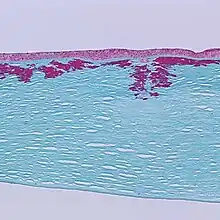

Mutations of the gene cause several forms of corneal dystrophies.[7][8]